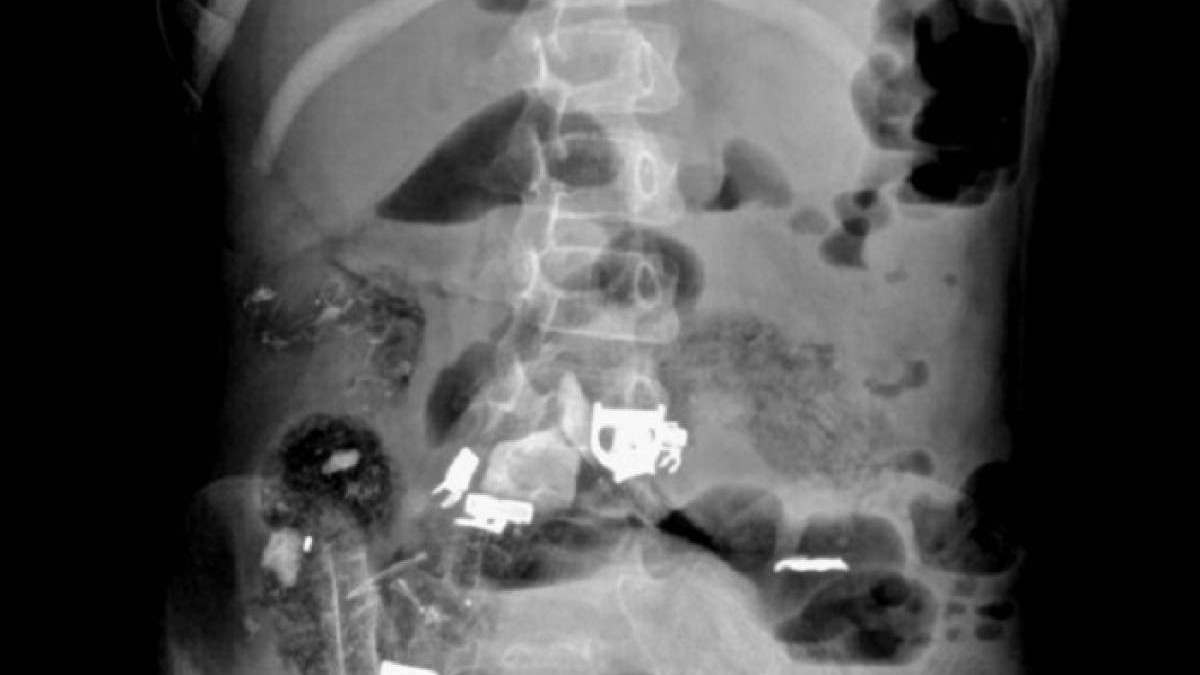

Ақтауда облыстық аурухана хирургтері 12 жастағы қыздың асқазанынан бір уыс шаш, қалам мен жабыстырғыш скотч алып шықты.

«Дәрігерлердің дер кезінде ота жасағанының көмегімен қыздың асқазаны тазартылды. Қажетсіз темір, қалам, скот, бір уыс шаш алынды», - дейді облыстық денсаулық сақтау басқармасының баспасөз қызметі.